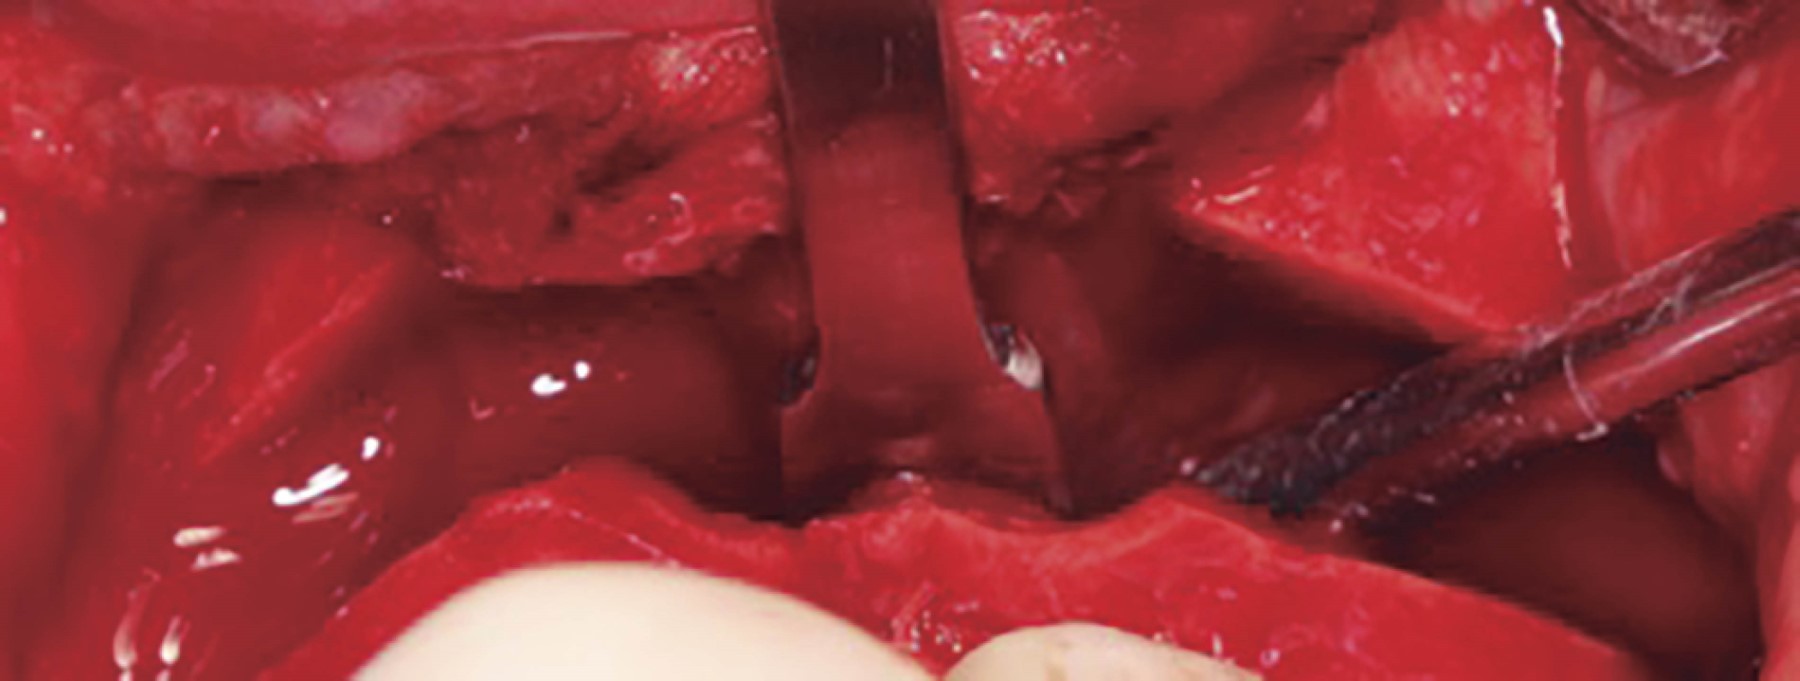

Se procede a la disección de la mucosa nasal. En el piso de la fosa nasal ha de disecarse hasta 30 mm a posterior (Figura 2) y enseguida se efectúa marcaje sobre el lecho óseo de acuerdo al tipo de osteotomía a realizar. Se colocan marcas de referencia (Figura 3). Se realiza osteotomía con sierra reciprocante, iniciando en la pared lateral de la apertura piriforme, protegiendo la mucosa nasal previamente con una legra, hasta la región pterigomaxilar. Una vez completado el corte se realiza la disyunción de las apófisis pterigoides laterales y mediales del seno maxilar mediante osteótomos y se procede a realizar el descenso maxilar introduciendo pinzas de Smith en la osteotomía del buttress maxilomalar (Figura 4), de manera gradual y verificando la integridad de la mucosa nasal. Se realiza este paso de manera bilateral. Se procede a introducir cincel de septum en la apertura piriforme (Figura 5). Se inserta la pinza de Smith en el buttress anterior y de igual forma se abre de manera gradual verificando también la integridad de tejidos blandos. Se completa la disyunción del maxilar y se moviliza en su totalidad: anterior, lateral e inferiormente (Figura 6). Se regularizan espículas, si las hay, y se reposiciona el maxilar de acuerdo a lo planeado para la cirugía. Se fija el maxilar con miniplacas de osteosíntesis en L en la región medial del buttress nasomaxilar y en el buttress cigomaticomaxilar ambos de manera bilateral, se verifica hemostasia y se colocan puntos de sutura en la mucosa maxilar. Se procede a seguir con la cirugía ortognática.2,6,14,15,19

Figura 6